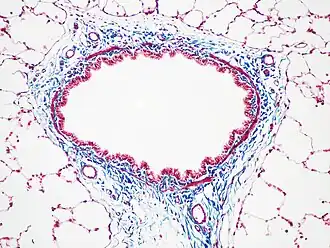

Окраска часто сочетается с окраской по Верхоффу. Эта комбинация красителей выделяет черным цветом эластин, что позволяет отличить мелкие артерии от вен.

Неалкогольная жировая болезнь печени, окраска трихромом Массона-Верхоффа